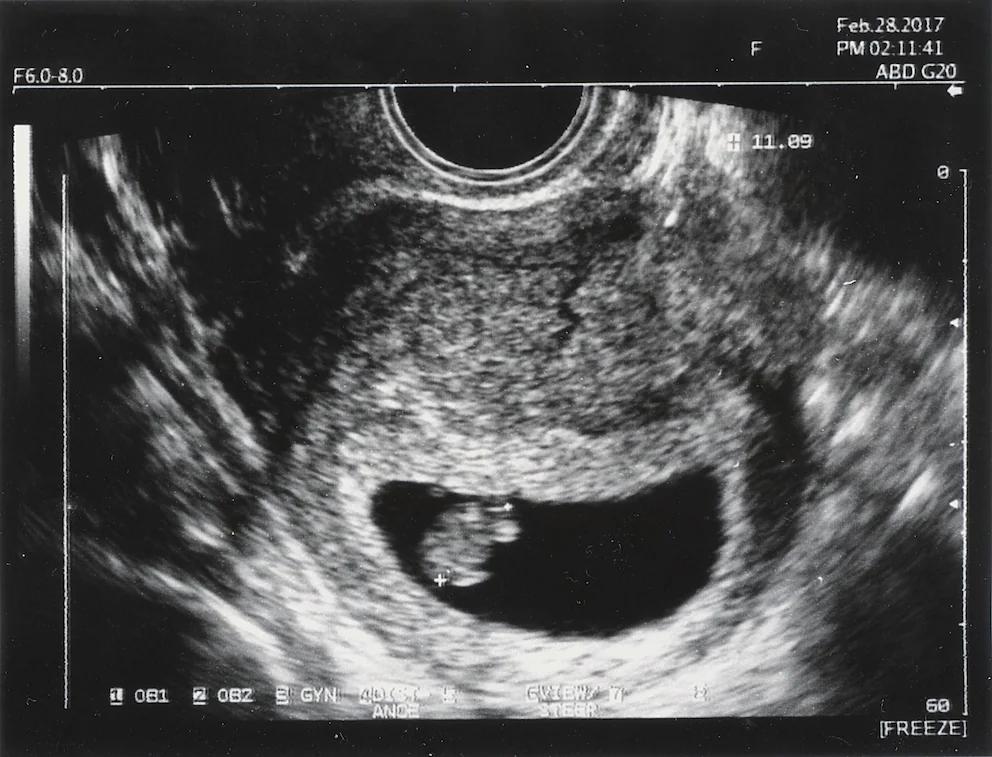

Der Begriff kein herzschlag in der Schwangerschaft bedeutet, dass das Herz des Embryos oder Fötus nicht mehr schlägt. Dies ist ein Zeichen dafür, dass die Schwangerschaft nicht mehr fortgesetzt werden kann und es zu einer Fehlgeburt kommt. Die Diagnose wird in der Regel durch eine Ultraschalluntersuchung gestellt.

Die Diagnose eines fehlenden Herzschlags wird in der Regel durch eine Ultraschalluntersuchung gestellt. Der Arzt kann den Herzschlag des Embryos oder Fötus ab der bis Schwangerschaftswoche sehen. Wenn kein Herzschlag festgestellt wird, wird die Diagnose kein herzschlag gestellt.

In einigen Fällen kann es vorkommen, dass der Herzschlag des Embryos oder Fötus nicht sofort erkennbar ist. In diesem Fall wird der Arzt eine weitere Ultraschalluntersuchung in einigen Tagen oder Wochen durchführen, um den Herzschlag zu überprüfen.